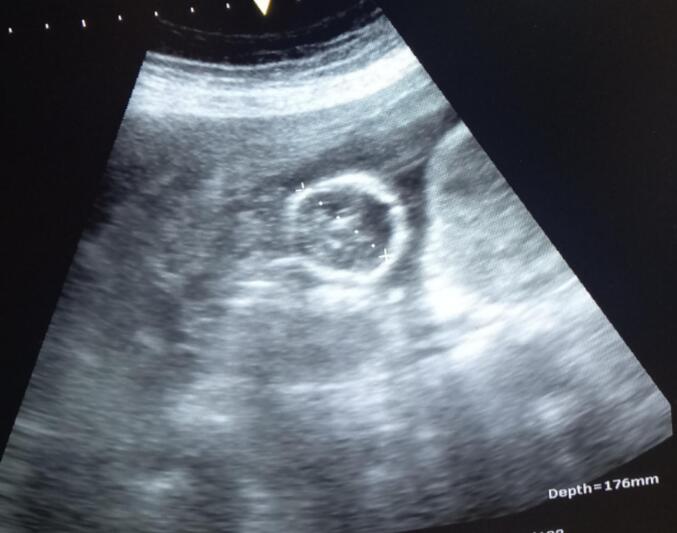

子宫破裂是一种罕见但严重的并发症,主要发生在妊娠晚期。在妊娠中期尤其罕见,特别是在存在子宫异常,如双角子宫或子宫双裂。本病例报告提出了一个重要的妊娠中期子宫破裂合并双角子宫的病例,导致约4000毫升危及生命的腹腔出血。病例报告详细介绍了该病例的临床表现、诊断挑战和治疗策略,强调了在类似情况下及时识别和干预的重要性,以改善产妇结局。

Uterine rupture is a rare but serious complication that predominantly occurs in the third trimester of pregnancy. It is exceptionally uncommon in the second trimester, particularly in the presence of uterine anomalies such as a bicornuate uterus or uterus didelphys. This case report presents a significant instance of second-trimester uterine rupture associated with a bicornuate uterus, resulting in a life-threatening intra-abdominal hemorrhage of approximately 4000 mL. The case report details the clinical presentation, diagnostic challenges, and management strategies used in this case, highlighting the critical importance of prompt recognition and intervention in similar scenarios to improve maternal outcomes.